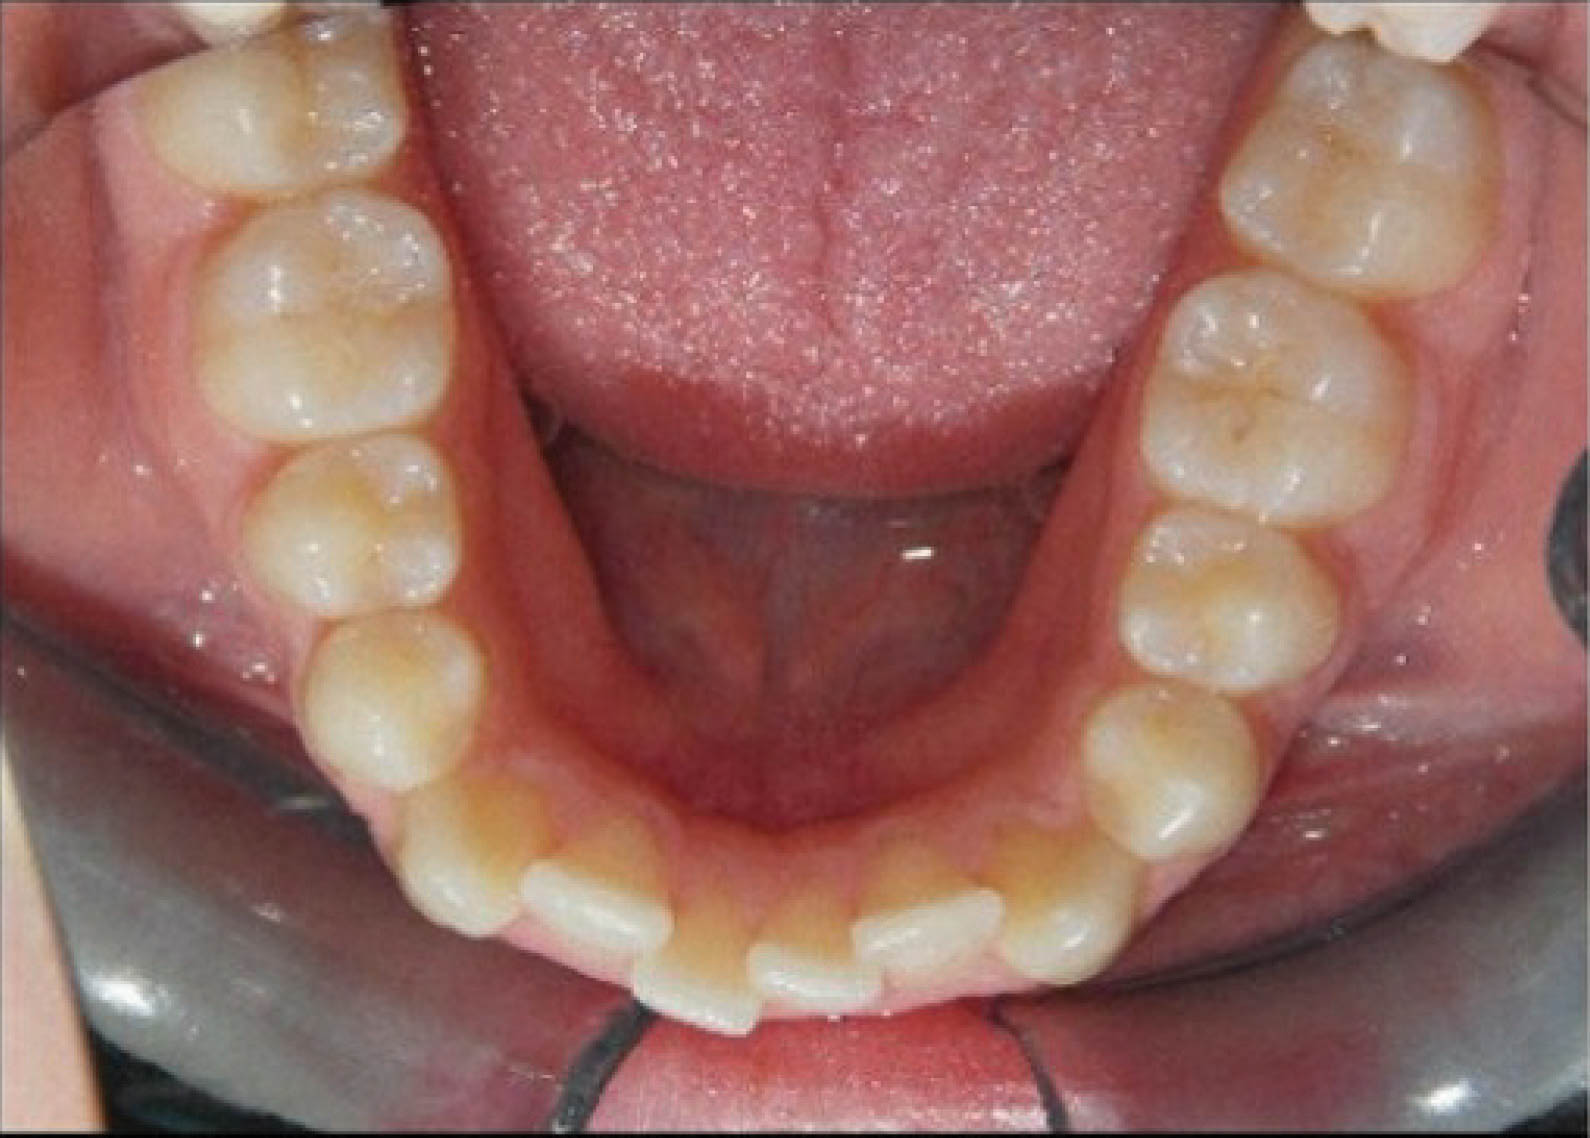

شکل 145-6 نحوه مرتب شدن دندانهای قدام پایین با 0.3mm استریپ هر کنتاکت را نشان میدهد. در پایان درمان قوس پایین کاملاً صاف شده است (شکل 146-6).

شکل 145-6